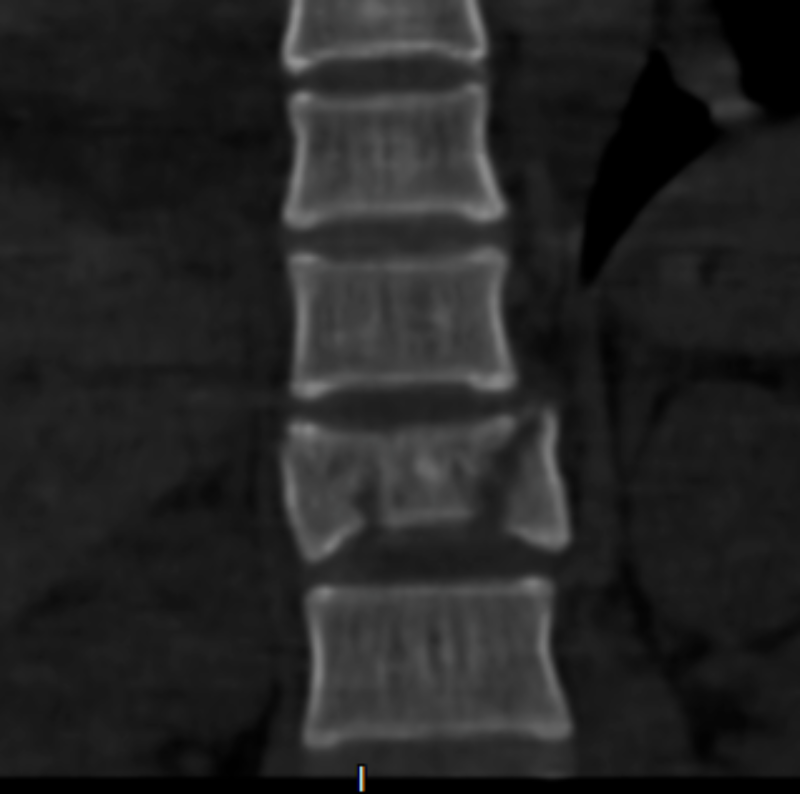

胸4椎體爆裂性骨折伴脫位